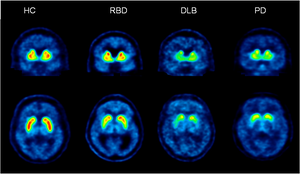

Detecting Parkinson's disease decades before symptoms appear

Researchers at The Florey and Austin Health have shown it is possible to detect tell-tale signs of Parkinson’s disease 20-30... read more >